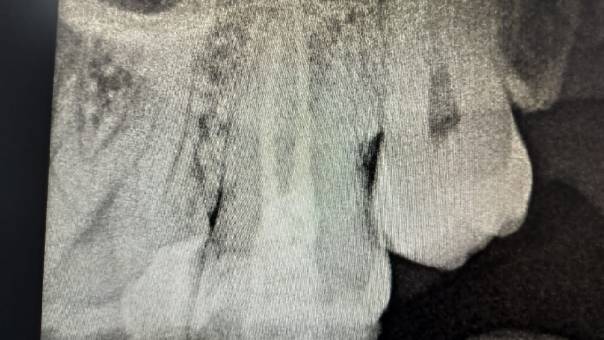

Clinical and Radiographic Findings:

On examination, mild tenderness was noted when

tapping on tooth 27. A radiographic evaluation

revealed that the distal canal of the tooth had been

inadequately treated and left unfilled. This had led

to a localized periapical infection.

Unfilled distal canal pre-operation